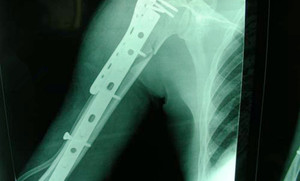

1、X线检查

常规X线摄片为肱骨干骨折主要影像学诊断手段,需要拍上臂正、侧位片,必要时还需要加拍肩关节及肘关节,可诊断并且确定骨折类型。

2、CT检查

本检查虽然不作为常规检查手段,但是对于肱骨干的复杂骨折或者螺旋形骨折有时需要进行CT扫描和三维重建,可做骨折复位的重要依据。

1、切开复位内固定

对于有以下情况者,需进行切开复位内固定手术。